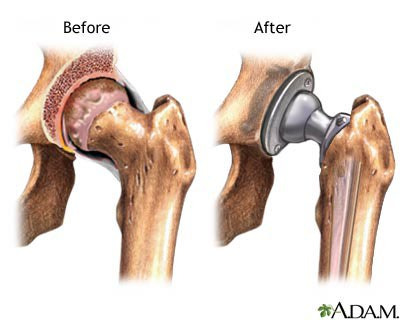

Στα πρώιμα στάδια της νόσου συνιστάται αποφυγή καταπόνησης, ελάττωση βάρους του σώματος λήψη αντιφλεγμονωδών φαρμάκων και συχνή παρακολούθηση. Εαν τα συμπτώματα επιδεινωθούν τότε γίνεται αναγκαία η χειρουργική θεραπεία.

Η χειρουργική θεραπεία περιλαμβάνει την αντικατάσταση της κατεστραμένης άρθρωσης απο μία τεχνητή και η συγκεκριμένη επέμβαση ονομάζεται αρθροπλαστική.

Πιο συγκεκριμένα η αρθροπλαστική είναι μια επέμβαση κατά την οποία αντικαθίσταται η κοτύλη συνήθως με μεταλλικό κύπελλο και η μηριαία κεφαλή από μεταλλική πρόθεση από τιτάνιο. Η τεχνική αυτή προσφέρει οριστική και άμεση λύση στο πρόβλημα της οστεοαρθρίτιδας